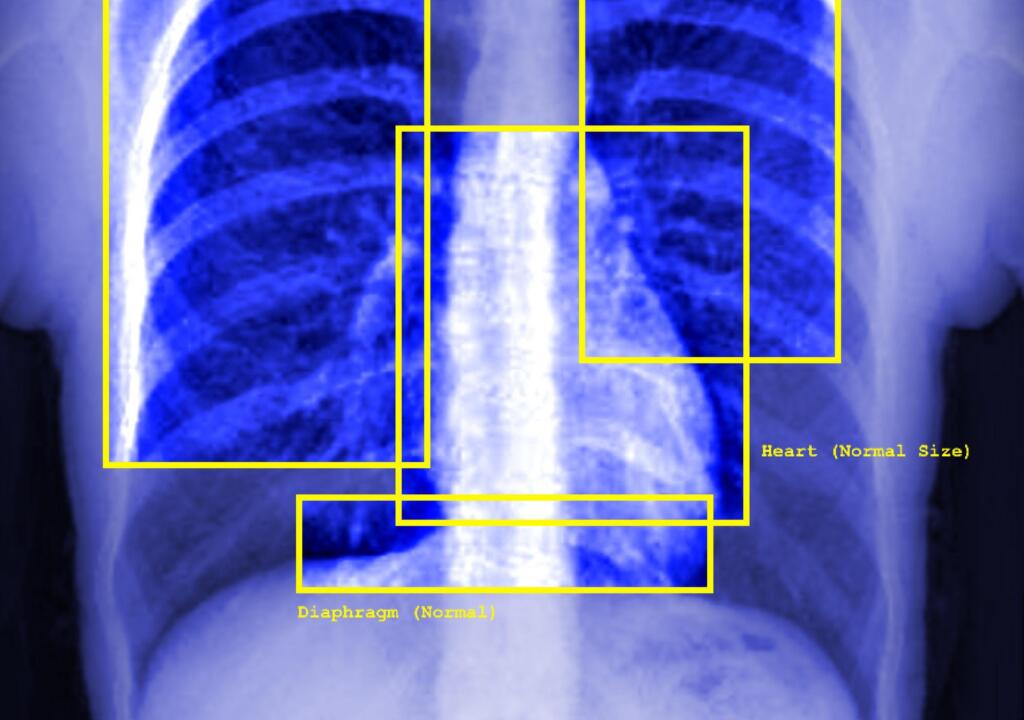

NL: Deze afbeelding toont een blauwe röntgenfoto van iemands borstkas - de ribben, de vage contouren van een hart en andere organen zijn zichtbaar. De afbeelding toont gele vierkanten rond de organen (linkerlong, luchtpijp, rechterlong, hart, middenrif) - elk met labels zoals: normaal, middenlijn, normale grootte. Rechtsonder staat in witte tekst 'geen afwijkingen gedetecteerd'.

EN: This image shows a blue xray image of a person's chest - it shows the ribs, the faint outline of a heart, and other organs. The image features yellow squares surrounding the organs (left lung, trachea, right lung, heart, diaphragm) - each of them feature labels such as: normal, midline, normal size. There is text in the right bottom corner in white which states 'no abnormalities detected'.